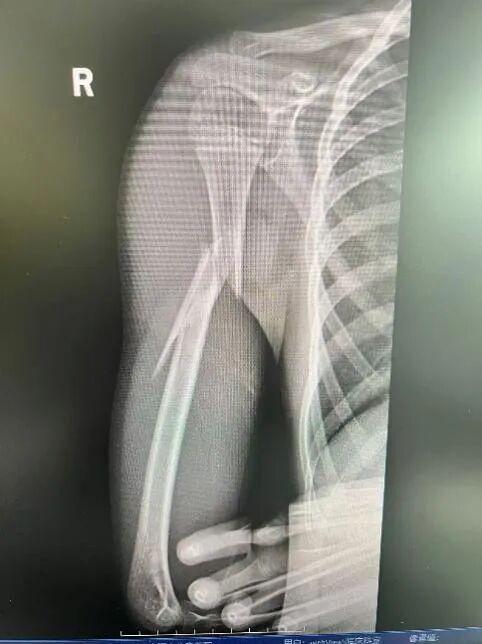

家长火速将孩子送往上海市儿童医院急诊,经急诊X光检查确诊为"右肱骨干粉碎性骨折"。

肱骨是上臂最粗壮的骨头,此类骨折通常伴随剧烈的疼痛和明显的畸形,还容易造成桡神经损伤,该神经一旦损伤,会造成永久性的功能障碍,包括无法抬手腕和翘拇指。

为最大程度减少手术创伤、避免损伤生长板、留下微小疤痕,骨科团队决定为其实施微创弹性髓内钉(TEN)固定术。与传统的大切口手术相比,这种技术仅需在骨折远端开两个微小切口,将具有良好弹性的钛合金髓内钉插入骨髓腔,像“支架”一样从内部将骨折断端对齐、固定。手术时间短、出血少、恢复快。